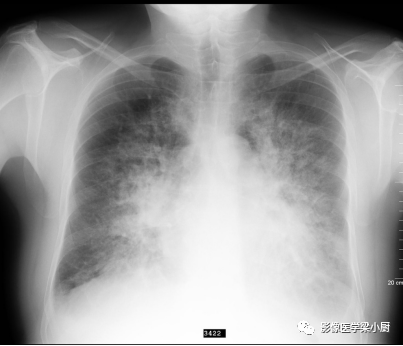

间质性肺水肿X线图像,双肺小叶间隔增厚,表现为双肺下叶几乎垂直于胸膜表面的短细的水平线,称为Kelery B线。